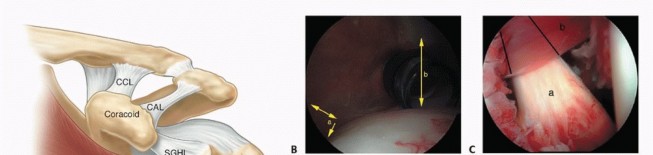

Arthroscopic Treatment of Anterior Shoulder Instability DEFINITION Glenohumeral stability depends on static a…